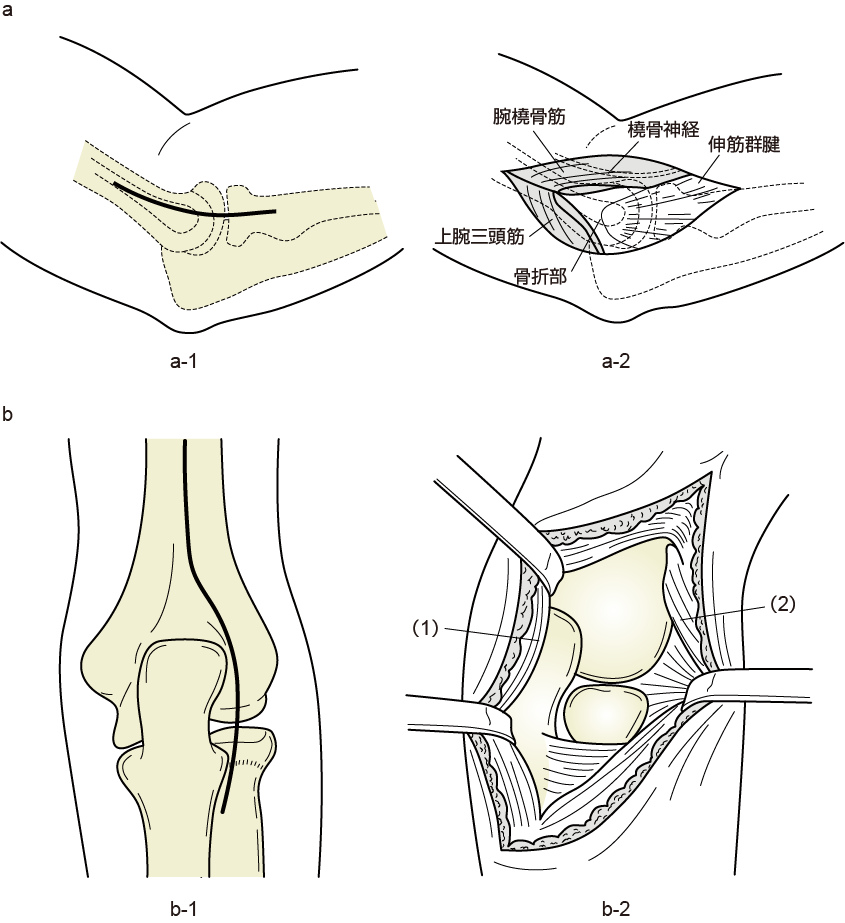

手術侵入法

a-1:外側侵入法(皮切)

a-2:外側侵入法(展開)

b-1:後外側侵入法(皮切)

b-2:後外側侵入法(展開)

出典

img

1: 著者提供